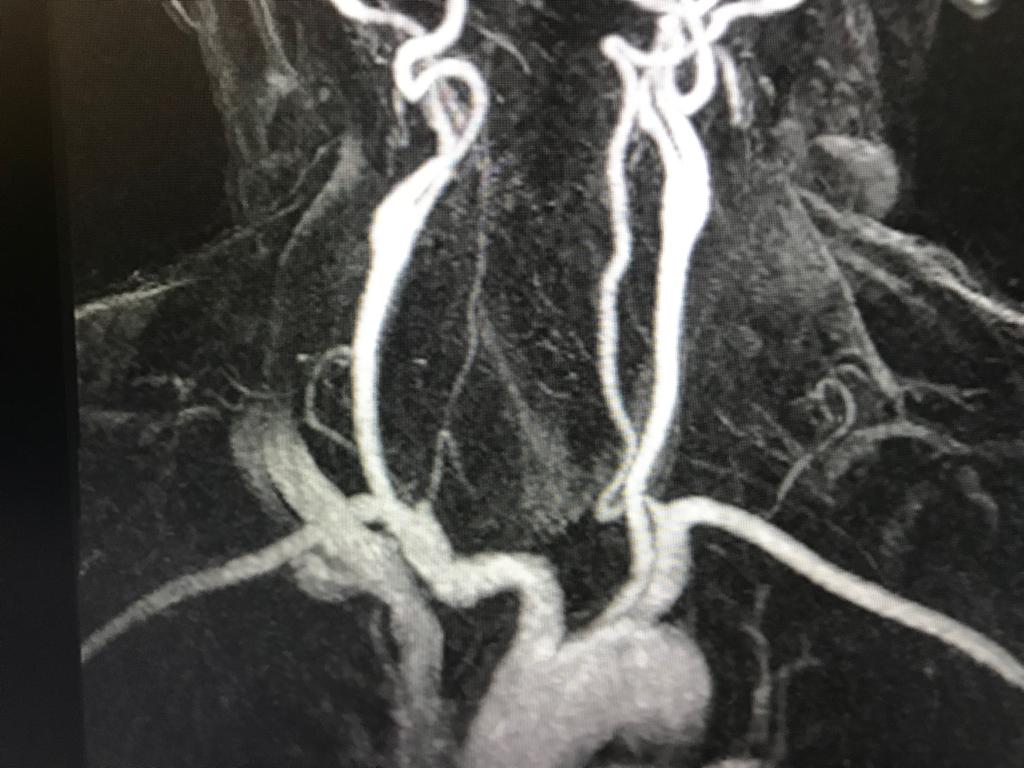

RM CEREBRAL

RM CEREBRAL Meningioma Lipomatoso: Es una variante atípica del meningioma. Los meningiomas constituye el tumor  intracraneal primario más frecuente (15-20%) y el tumor extraparenquimatoso más frecuente en el compartimento supratentorial en el adulto. Es por tanto una...